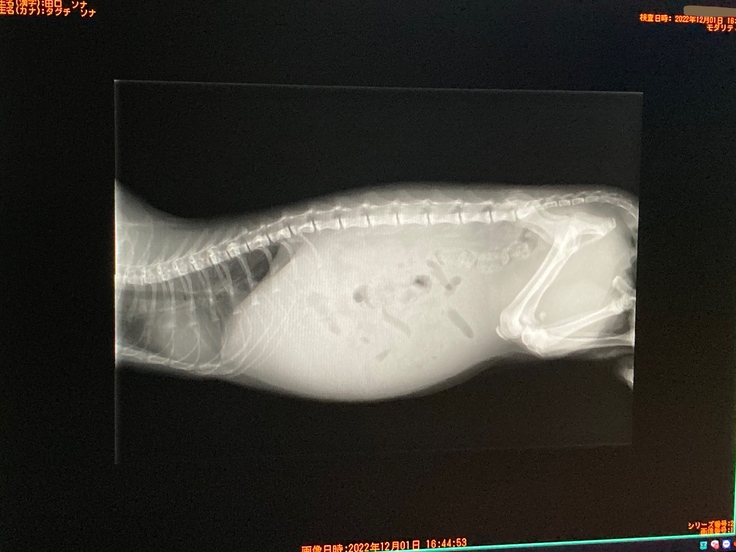

セカンドオピニオン病院 レントゲン結果↓(靄がかかった様に映るのは腹水だそうです)

ソナは腹水も溜まっていて、右腎臓の内側に2.5cm程の肉芽腫がある為、混合タイプでした。